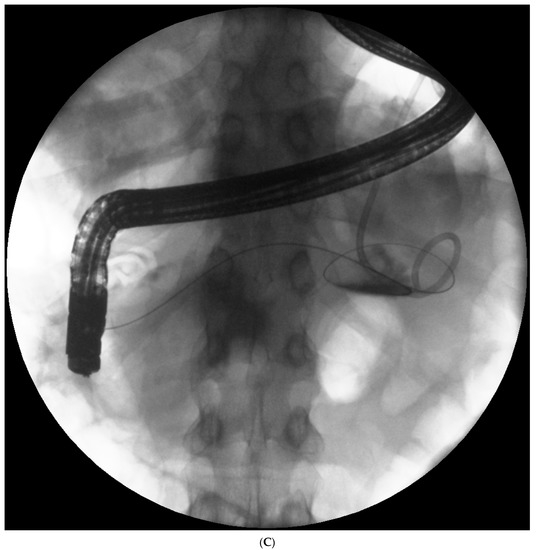

Endotherapy for post-inflammatory pancreatic and peripancreatic fluid collections (Figure 1A–L) is a recognized, minimally invasive treatment method [6][7][8]. Transpapillary endoscopic drainage involves accessing the collection through the major duodenal papilla if the main pancreatic duct communicates with the collection [6][10][11][12][13]. Active transpapillary drainage involves the introduction of a nasal drain and a pancreatic stent through the major duodenal papilla with their distal ends passing through the site of disruption into the lumen for the fluid collection [6][10][11][12][13]. Subsequently, the collection is rinsed with a saline solution through the drain. Passive transpapillary drainage involves the introduction of a stent into the main pancreatic duct, which is important for endotherapy for main pancreatic duct disruption [6][10][11][12][13]. The size and length of the pancreatic stent should be selected individually according to the fluoroscopic image of the main pancreatic duct during endoscopic retrograde pancreatography. Main pancreatic duct stenting (passive transpapillary drainage) is designed to ensure the free outflow of pancreatic juices by physiological means into the duodenal lumen and, consequently, to prevent the juices from escaping through the injured duct into the collection, thus increasing its volume. Moreover, inserting a stent into the pancreatic duct (Figure 2A–C) is supposed to create conditions that promote healing and stop pancreatic juice leakage by bridging the disrupted part of the duct.

Figure 1. (A–L) Endoscopic treatment of walled-off pancreatic necrosis. In the second week of acute necrotizing pancreatitis, the acute necrotic collection (A) is visible in the abdominal contrast-enhanced computed tomography (CECT), which evolved in the sixth week of the illness duration into the symptomatic walled-off pancreatic necrosis (B). Patient qualified for endoscopic treatment (C–F) transmural drainage using the self-expanding metal stent (C,D) and endoscopic necrosectomy (E,F) was performed. In the second week of endotherapy, the endoscopic retrograde pancreatography (G–J) was performed. During pancreatography, the complete pancreatic duct disruption was stated (G–I) and transpapillary drainage was carried out (J). After achieving the treatment’s success and the complete regression of the necrotic collection, the transpapillary stent was observed in the bottom of the collection via the endoscopic view from the stomach’s side through the transmural stent (K). Control CECT confirmed the total regression of the collection (L).

Figure 2. (A–C). Endoscopic treatment of the pancreatic pseudocyst. Transmural drainage using plastic stents was performed (A,B). The endoscopic retrograde pancreatography (C) was performed. During the pancreatography, complete disruption of the pancreatic duct was stated (C). Transpapillary access to the pseudocyst was achieved (C). Transmural access to the same collection was stated (A,B).